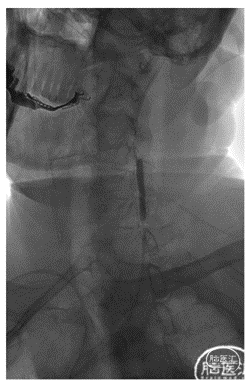

经对侧桡动脉置6F动脉鞘,行对侧低位椎动脉支架置入示意图:

2、可选择对侧桡动脉置入6F动脉鞘,单弯或西蒙导管将0.035泥鳅导丝置于病灶侧锁骨下动脉起到牵拉作用。

3、将6F导引导管到达狭窄椎动脉附近,微导丝导引球囊扩张支架(4-5mm)铆定狭窄部位后扩张释放支架。

备注:6F导引导管可兼容0.035 in泥鳅导丝和球囊扩张支架(4-5mm),5mm支架通过略涩。